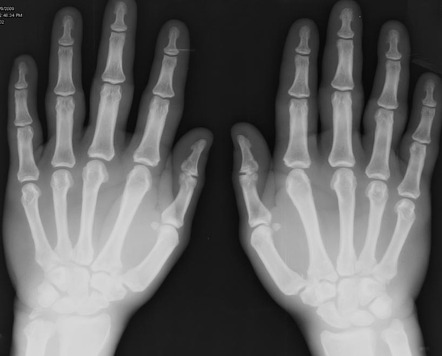

Oase. Acromegalia

Acromegalia este o afecțiune caracterizată de creșterea exagerată a oaselor extremităților și ale feței, determinată de o secreție excesivă de hormon de creștere.